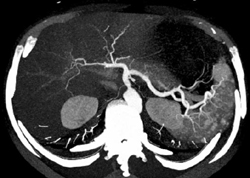

Pancreatic Cancer Occludes Splenic Arteries and Vein With Splenic Infarction